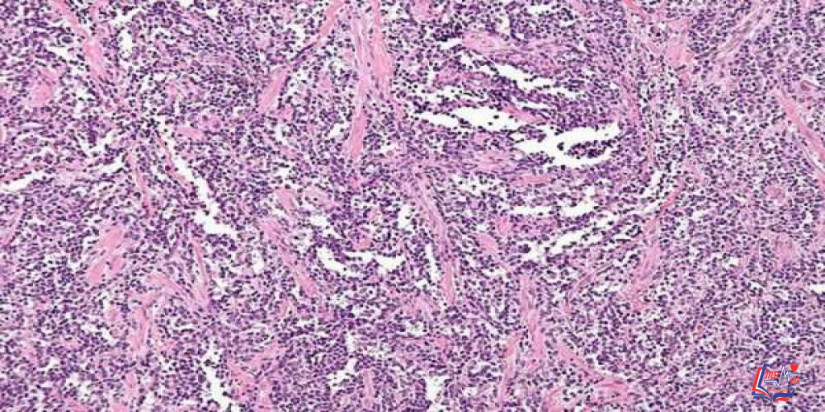

سرطان الثدي الانتشاري Invasive lobular carcinoma

سرطان الثدي الانتشاري أو سرطان الثدي الانتشاري أو الغَزوي، هو نوع من أنواع سرطان الثدي يبدأ في الغدد المنتجة